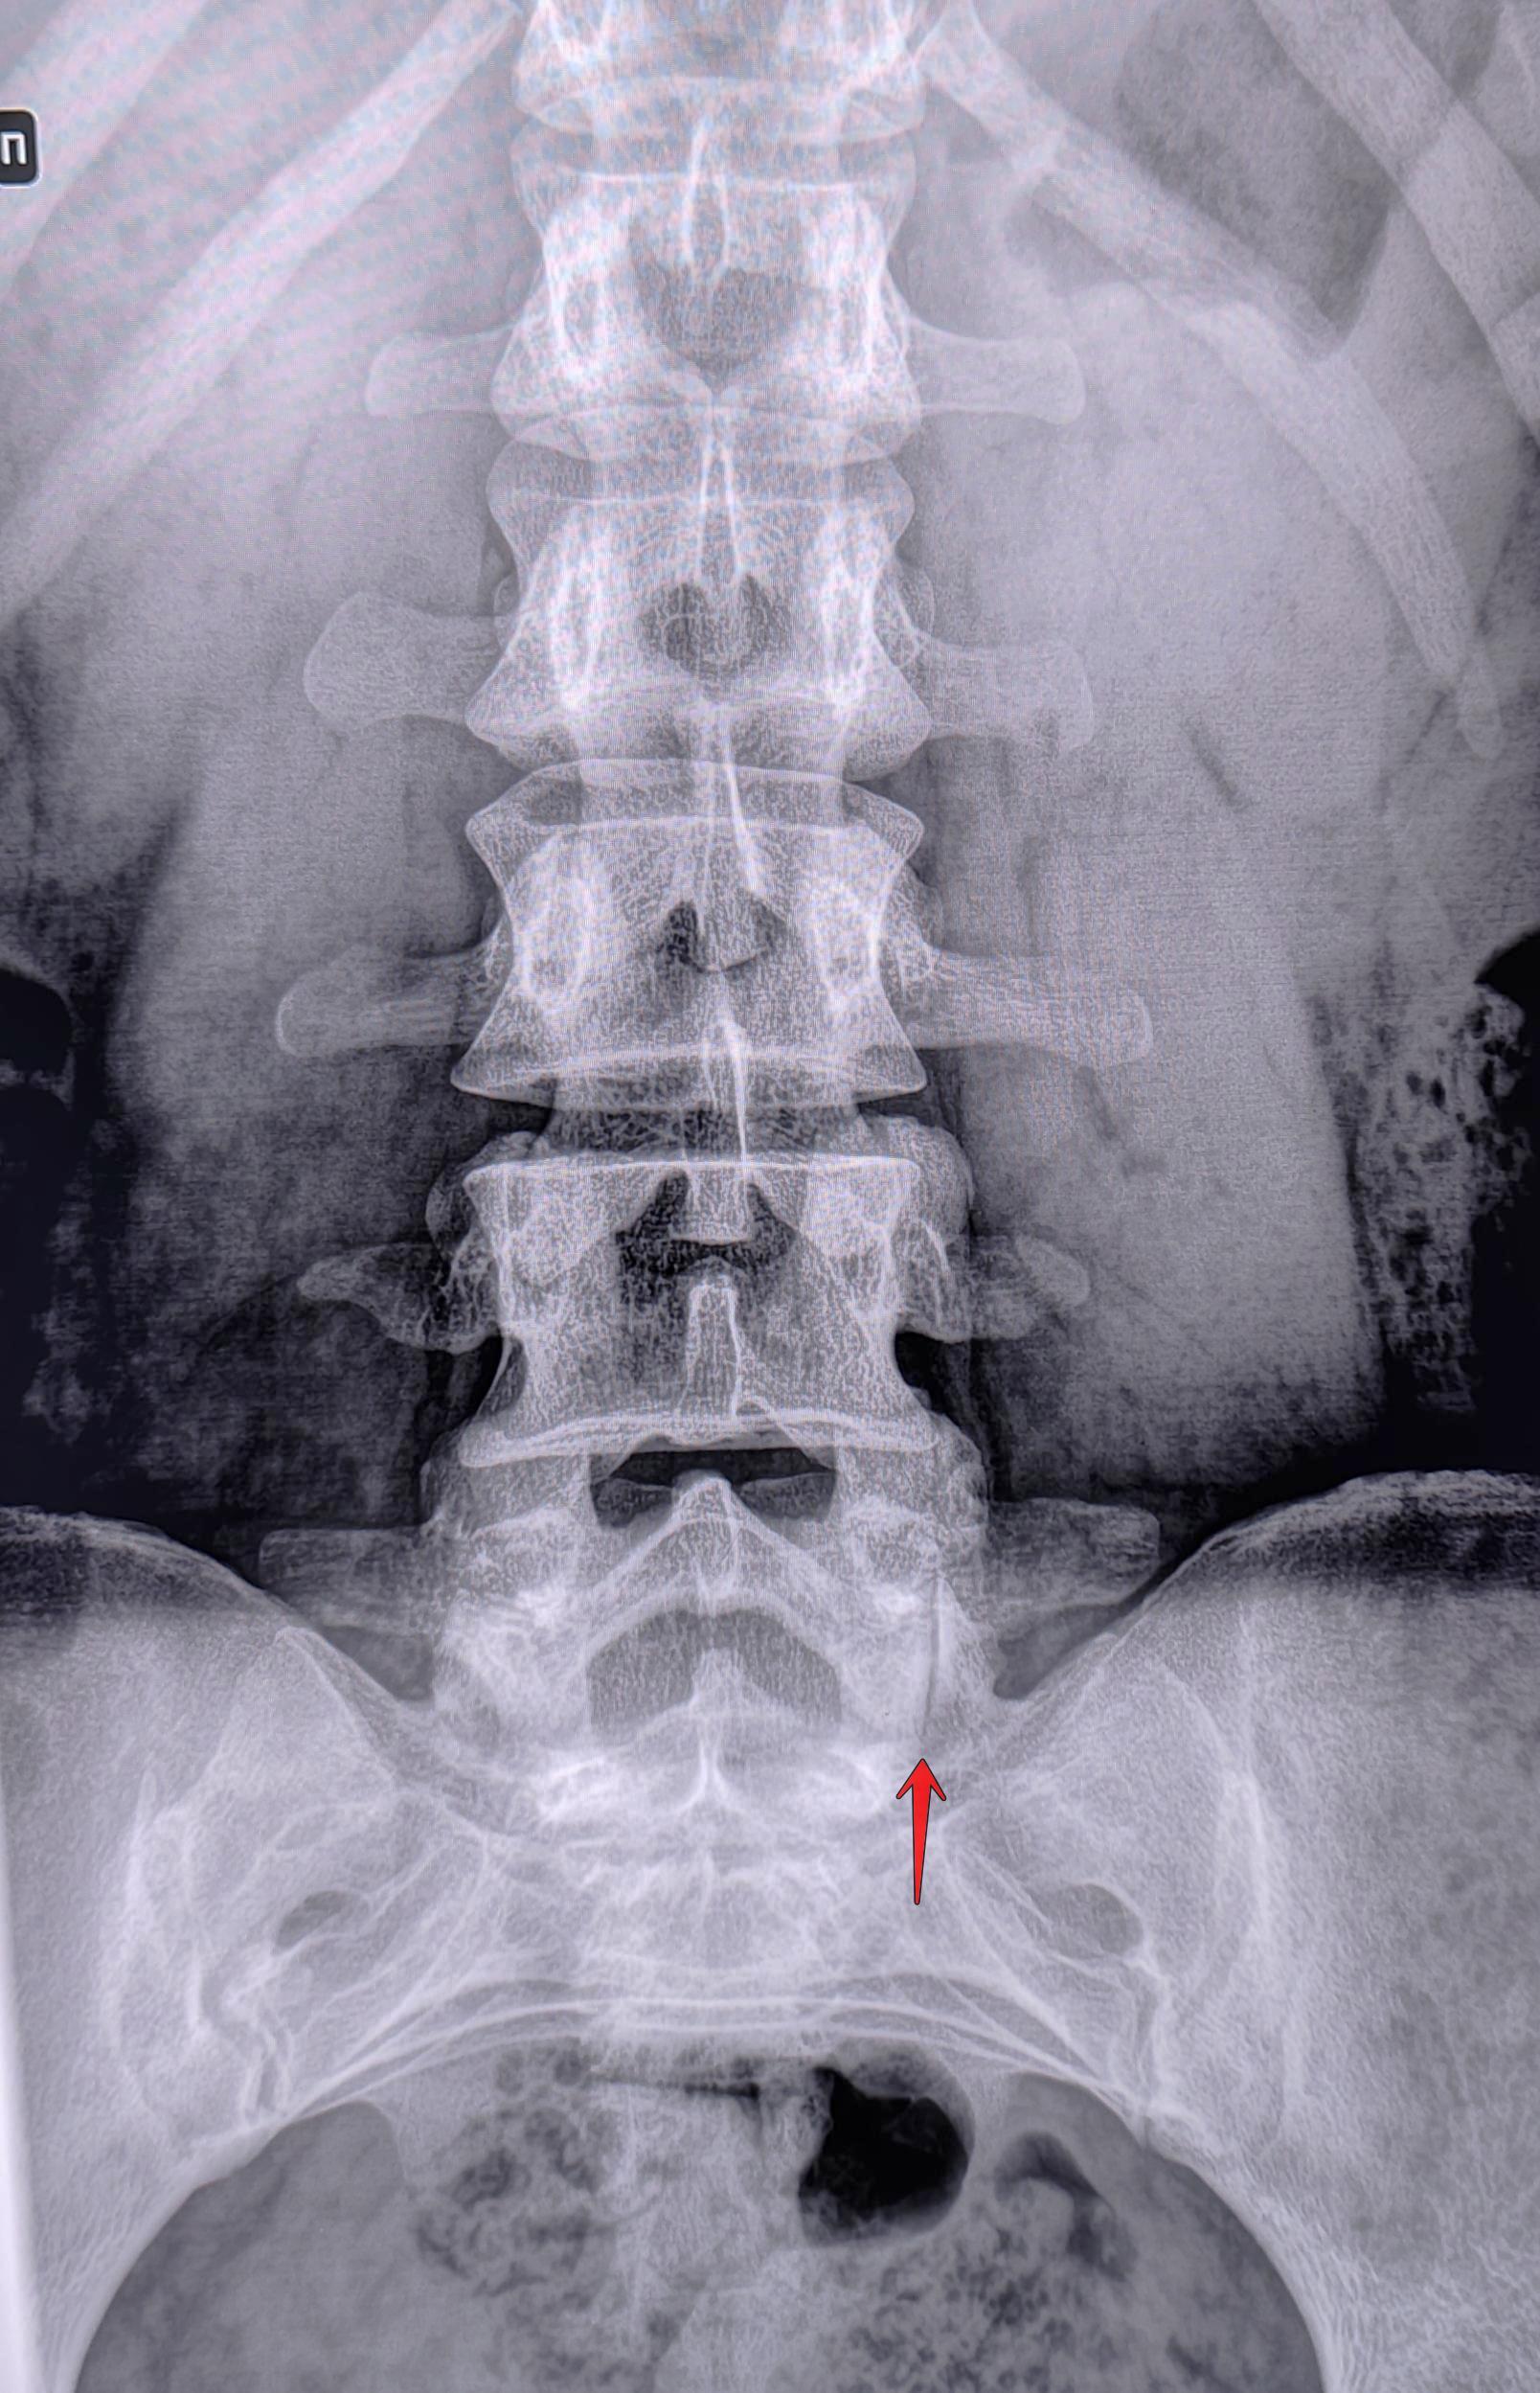

Визуализируется левосторонний дефект дуги L5 позвонка, соотношение задних отделов тел позвонков не нарушено(спондилолистез отсутствует),межпозвонковые щели не сужены, субхондральный склероз замыкательных пластин отсутствует, краевые остеофиты тел позвонков не выявлены. Заключение: Левосторонний спондилолиз L5 позвонка.